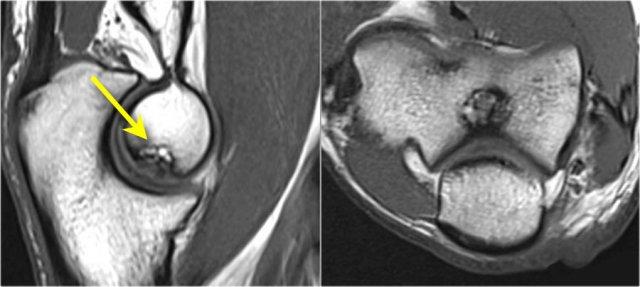

Pseudodefect of the capitellum

Đây là một phát hiện mà bạn thường thấy trên các hình ảnh mặt phẳng coronal.

Trông có vẻ giống như một tổn thương sụn xương, nhưng nếu bạn nhìn vào hình ảnh mặt phẳng sagittal, bạn sẽ nhận thấy rằng hình ảnh mặt phẳng coronal đi qua phần không có khớp phía sau của chỏm con.

Vì vậy, khi khuỷu tay duỗi hoàn toàn, một phần của chỏm quay thực sự nằm phía sau bề mặt sụn khớp của chỏm con.

Trên hình ảnh mặt phẳng coronal, chúng ta sẽ quan sát thấy chỏm quay được bao phủ bởi sụn và đối diện với nó là phần không được bao phủ bởi sụn của chỏm con, phần này thường có phần không đều.

Pseudo-loose body

Một phát hiện phổ biến khác là một mảnh mỡ nhỏ mà bạn sẽ thấy trên hình ảnh mặt phẳng đứng dọc, trông giống như một dị vật nhỏ tự do hoặc một khuyết sụn.

Điều này có thể được giải thích nếu chúng ta nhìn vào bề mặt khớp của mỏm khuỷu.

Thông thường mỏm khuỷu có hai mảnh sụn với một vùng nhỏ ở giữa, được lấp đầy bởi mỡ.

Plica

Cấu trúc này ở phía bên ngoài của khớp đôi khi được nhìn thấy và là một nếp gấp hoạt dịch (plica).

Nó có thể nổi bật và trông gần giống như một sụn chêm.

Đây là một cấu trúc bình thường, nhưng đôi khi nó bị dày lên hoặc không đều và có thể là nguyên nhân gây ra các triệu chứng.